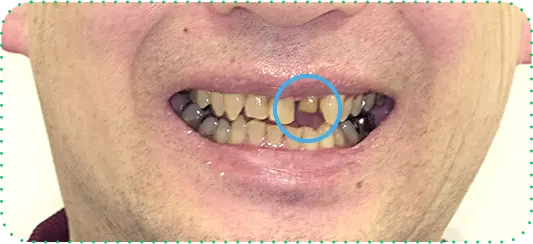

主訴

前歯をインプラントにしてほしい

治療期間

8か月

治療費

約150万円

治療内容

右上1番と左上1番をインプラント、右上2番をラミネートべニア、左上2番をセラミッククラウンにて修復

治療のリスク

治療後に口腔内管理が不適切な場合、埋入したインプラントが感染・炎症を起こす可能性があります。

しみたり、違和感が生じることがあります。咬み合わせによっては、セラミックが欠ける可能性があります。